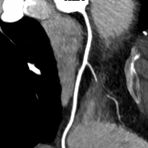

Hals

• Darstellung der Blutgefäße (sog. CT- Angiographie)

• Darstellung der großen Gefäße zur Erkennung von Gefäßverschlüssen (z. B. Mesenterial - Arterienembolie oder Einengungen von Gefäßen (z. B. Nierenarterien)

• Darstellung und Therapieplanung von Aneurysmen (CT- Angiographie)